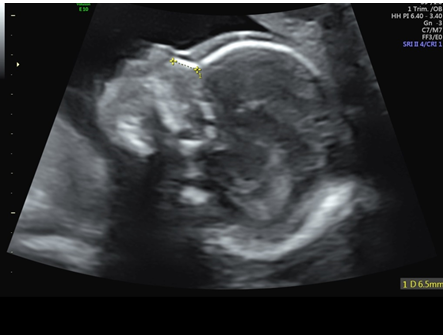

Chen FC et al. Detection of Spina Bifida by First Trimester Screening – Results of the Prospective Multicenter Berlin IT-Study, Ultraschall in Med 2017; 38: 151–157

IT Beispielbild

IT / CM / BS Anleitung Messung

IT / CM / BS Tabelle Normwerte